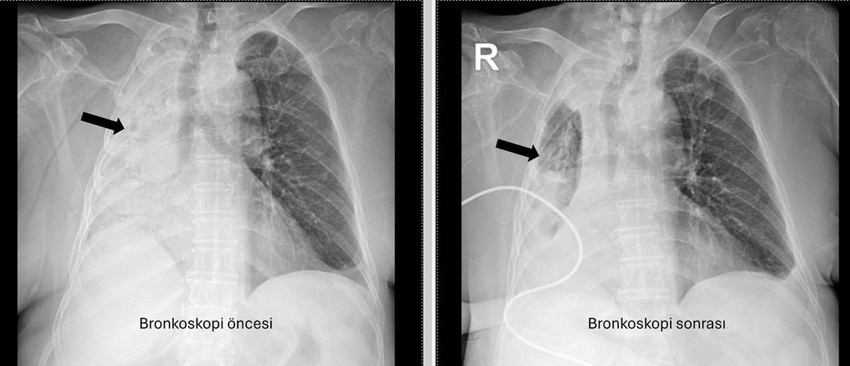

Denizli’de 78 yaşındaki felçli hastanın nefes borusuna kaçan mısır tanesi 5 ay sonra ortaya çıktı. Akciğerine enfeksiyonu şikayetlerinin tekrarlamasıyla ortaya çıkan olayda, yaşlı kadının sağ akciğerinin tamamen kapalı olduğu anlaşıldı.

Denizli’de yaşayan ve emekli öğretmen olan 78 yaşındaki felçli kadın son zamanlarda sık sık akciğer enfeksiyonu nedeniyle hastaneye gidiyordu. 1 ay önce gittiği hastanede bronkoskopi yapılmasına rağmen sorun saptanmadığı öğrenildi.

Yaşlı kadının son gittiği hastanede sağ akciğerinin tamamen kapandığının tespit edilmesi üzerine Pamukkale Üniversitesi Hastanesine başvuruldu. Prof. Dr. Göksel Altınışık Ergur, tarafından yapılan tetkiklerde sağ akciğere giden hava yolunun bütünüyle kapalı olduğu görüldü.

Hastaya acil bronkoskopi planlanıp hemen işlemin gerçekleştirildiğini söyleyen Prof. Dr. Altınışık Ergur, "Fleksibl (esnek, eğilip bükülebilir) bronkoskop ile hava yolları incelenirken çok yoğun ve koyu sekresyon olduğu, bunun iyice temizlenmesi sonucunda ancak hava yollarının incelenebileceği görüldü. Aspiratör (içerideki salgıları emmeye yarayan bir cihaz) sayesinde hava yollarına steril sıvı verilip emilerek bu temizlik yapıldı. Sonrasında sağ akciğere giden hava yolunda sarı bir nesne olduğu görüldü. Bu hâliyle yabancı cisim olduğu anlaşıldığı gibi bunun mısır tanesine benzerliği de açıktı. Yabancı cismi çıkarma işlemi genel anestezi altında, rijit bronkoskop ile yapılmak üzere planlanabilirdi; çünkü bu durumun tedavisi yabancı cismin oradan, ek sorun oluşturmaksızın çıkarmaktı. Ancak, genel anestezi altındaki bir işlem için hastanın genel durumu bozuk olduğundan, özellikle ek hastalıkları ve enfeksiyon varlığı ile işlem riski artacağından hastadaki cismin fark edildiği sırada çıkarılmasına şans vermek daha uygun görüldü. Hava yolu içindeki sıvıları emen aspiratörün gücünü kullanılarak cismin çıkarılması mümkündü. Bronkoskobun ucu, sarı cismin gövdesine dayanıp aspiratör ile emme sayesinde ikisi birbirine sımsıkı yapıştırıldı. Emme gücünün azaltılmamasına dikkat ederek yabancı cisim ve bronkoskop, aynı zamanda hava yollarından dışarıya başarı ile çıkarıldı. İşlem sonrasında hasta yakınına mısır tanesi açısından tıbbi öykü yeniden sorulduğunda, hastamızın bundan beş ay önce yediği pizzanın üzerinde mısır taneleri olduğu öğrenildi. O sırada ani bir yakınma ortaya çıkmadığı için böyle bir ihtimal akla gelmemişti. Düşkün hastalar taneli gıdalar yerken, bu durumun fark edilmeden de gelişebileceğini göstermesi açısından önemli olan bu tablo, hastaların bir dedektif titizliği ile değerlendirilmesi gerekliliğini bir kez daha ortaya koymaktadır" dedi.